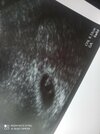

bosko! Ja ide w poniedziałek. Bete mam dzisiaj 750 (niby rowny 4tydzien skonczony) ciekawe co bedzie u mnie na usgJa już po wizycie, jest serduszko![]()

Koniec 4 z moich obliczeńKtóry miałaś tu tydzień?![]()

Tak jak @vaniliova powiedziała będzie dobrze i jest dobrze! Cudowne wieści, niech maluszek rośnie zdrowoJestem po wizycie! Serce bije![]()

Dziękuję wamTak jak @vaniliova powiedziała będzie dobrze i jest dobrze! Cudowne wieści, niech maluszek rośnie zdrowo![]()